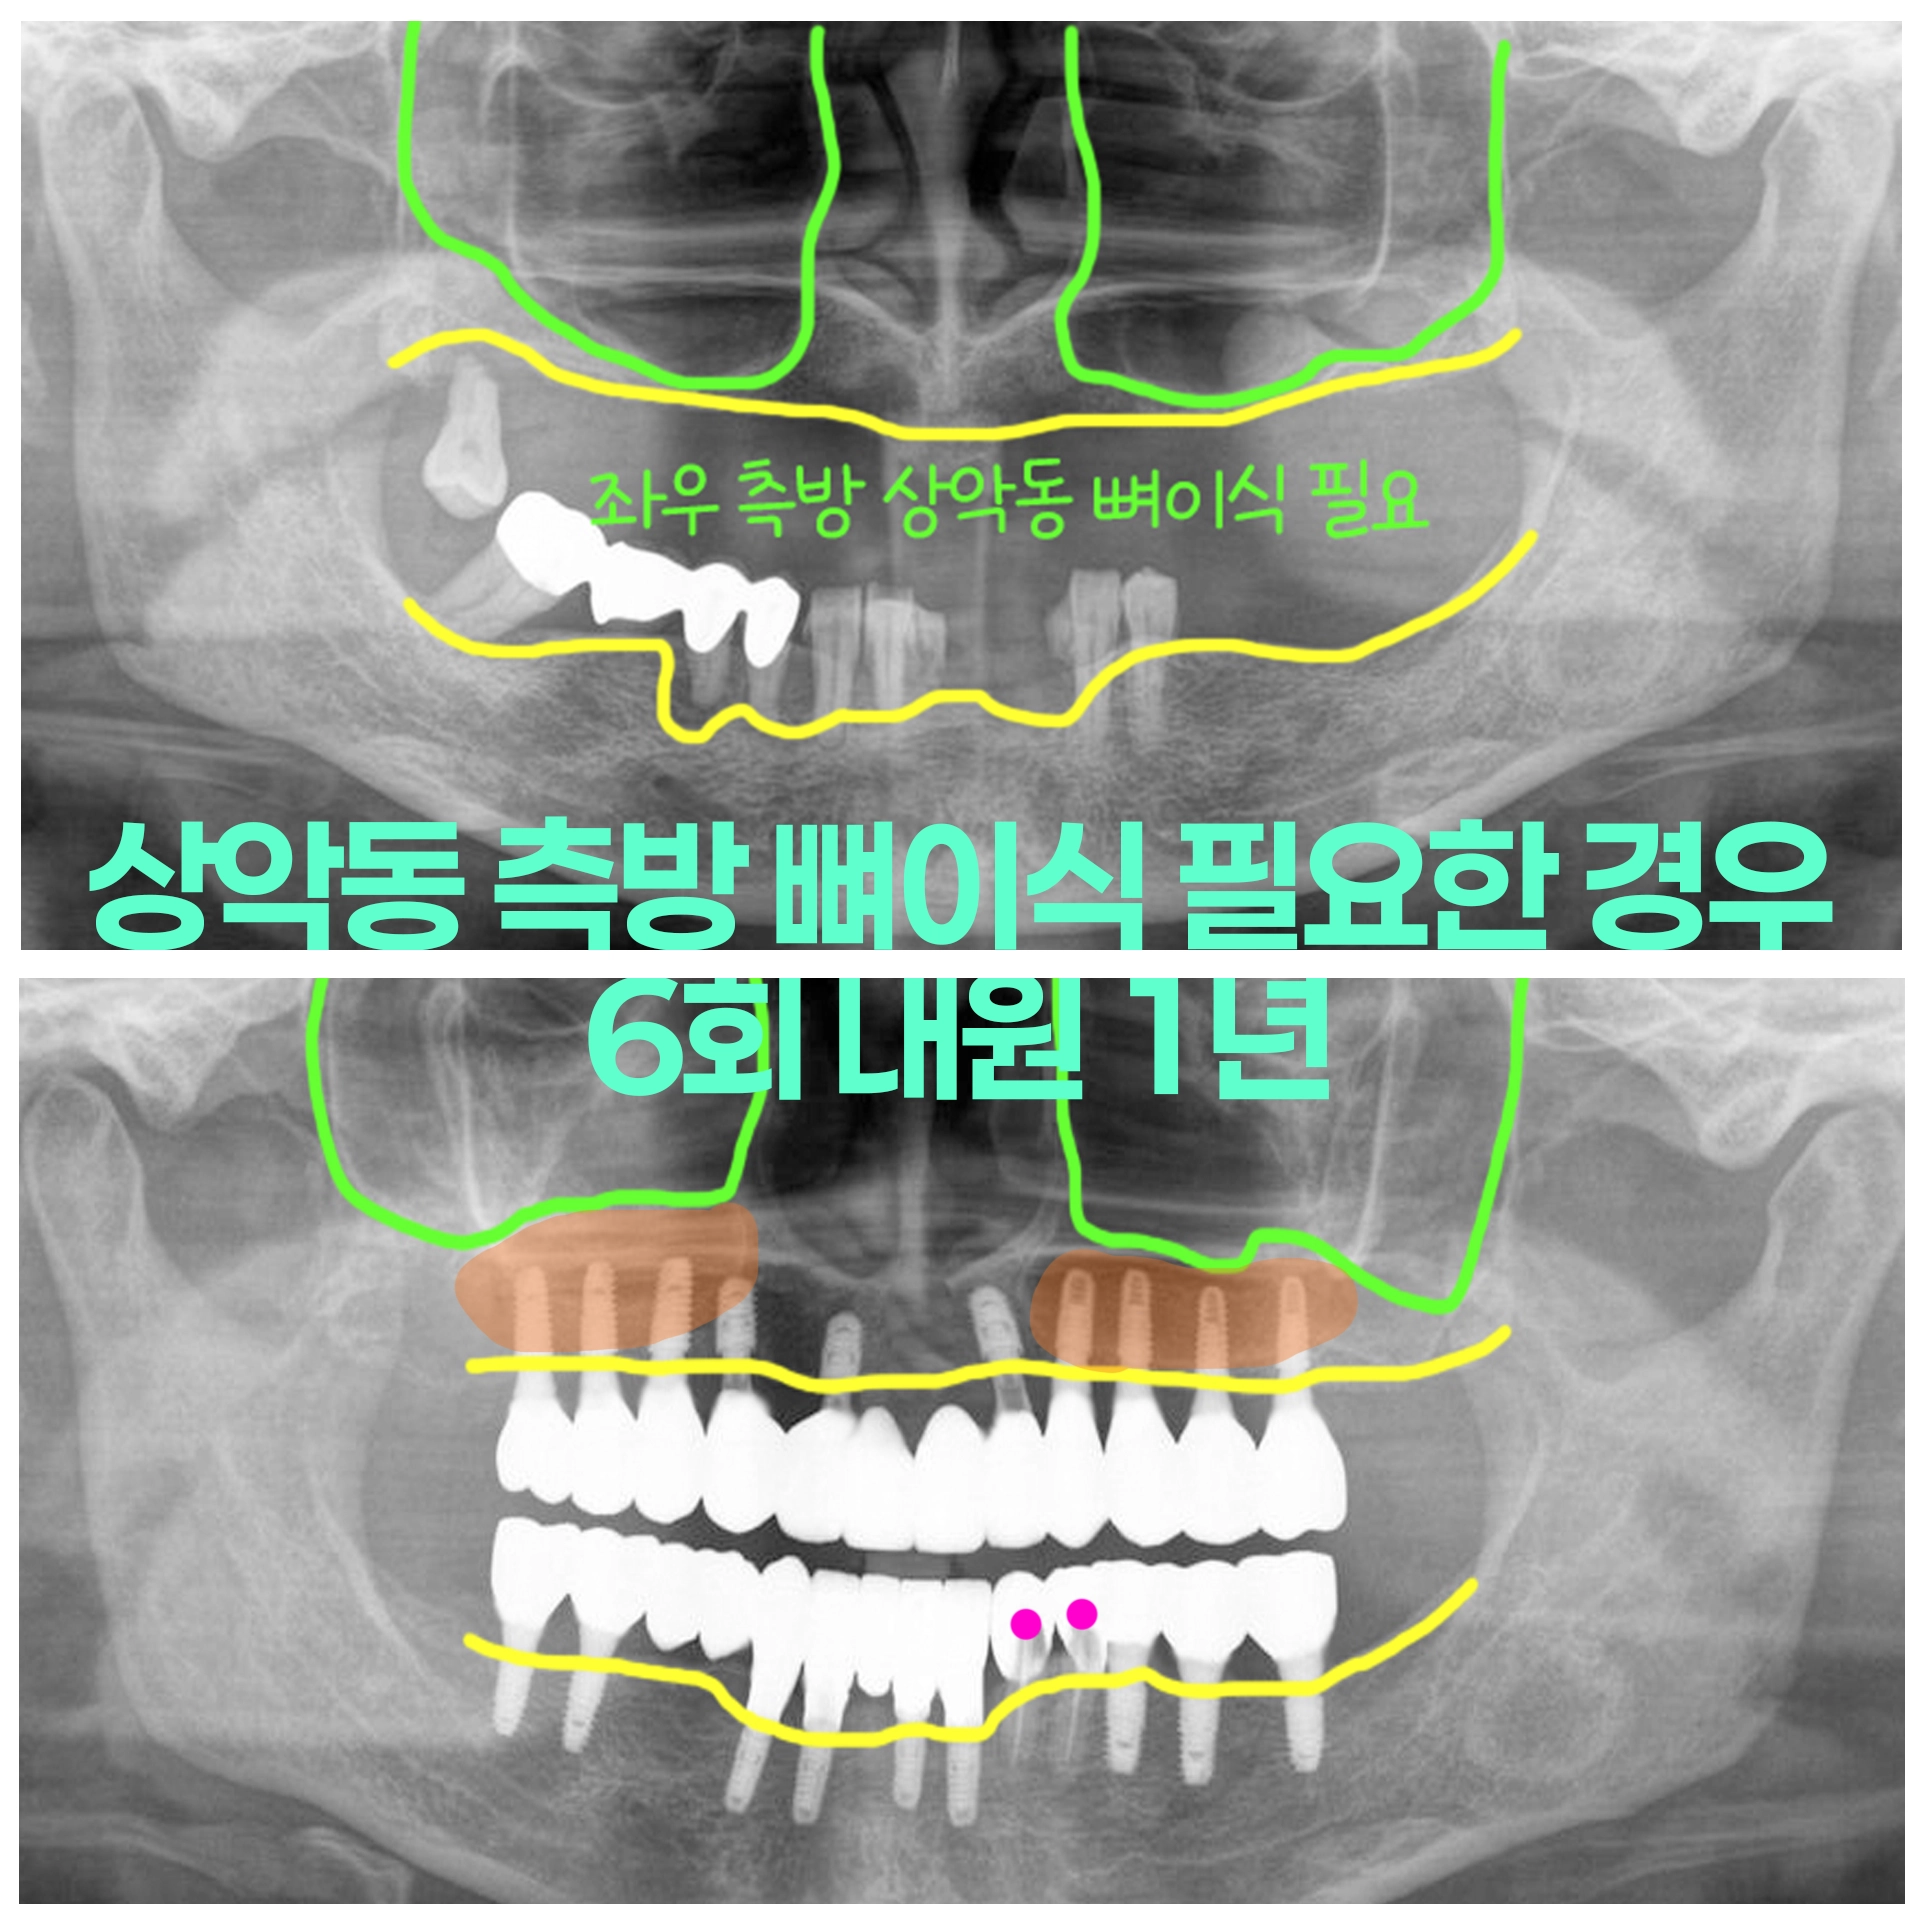

50대 여성 심한 치주염 치아 발치후 상악동 윈도우뼈이식 즉시하중 당일임시치아 전체임플란트